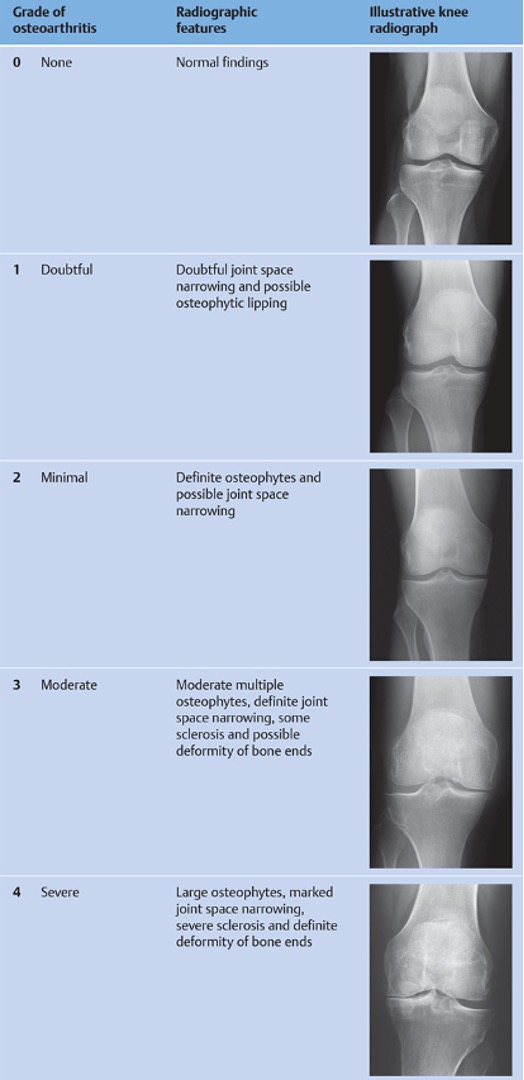

According to the Kellgren-Lawrence classification, grade 3 osteoarthritis features moderate multiple osteophytes, definite narrowing of the joint space, some sclerosis, and possible deformity of bone ends, which is best depicted in Figure 5.

The Kellgren-Lawrence (KL) classification is the most commonly used system for radiographic interpretation of osteoarthritis (OA) in the knee. Kellgren and Lawrence originally studied radiographic findings of osteoarthritis in coal miners in 1952 and noted the common radiographic findings associated with osteoarthritis. The two authors later developed their five-grade classification system to delineate the severity of OA on radiographic images. The grading system is as follows:

Grade 0: No radiographic signs of OA.

Grade 1: Doubtful narrowing of joint space and possible ostephytic lipping.

Grade 2: Definite osteophytes and possible narrowing of joint space.

Grade 3: Moderate multiple osteophytes, definite narrowing of joint space, some sclerosis, and possible deformity of bone ends.

Grade 4: Large osteophytes, marked narrowing of joint space, severe sclerosis, and definite deformity of bone ends.

Classically, Kellgren and Lawrence described grades 2 or less as none or possible OA and grades more than 2 as definite or mild OA. This classification system helps clinicians assess the severity and progression of OA, report data for epidemiologic studies, and guide treatment decisions.

Illustration A is a table with descriptions and example radiographs of the Kellgren-Lawrence classification of osteoarthritis.